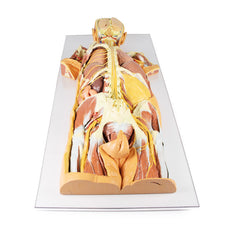

3D Printed Thoracic Cross Section at T6

This model is a cross-section of the thorax at the level of the T6 vertebra. Beginning posteromedially at the spinal

cord within the vertebral canal, then moving radially, the costovertebral joints of the 6th ribs are visible,

followed by several other ribs around the margin of the thoracic cavity, a pair of which unite anteriorly with the

sternum via the costosternal joints. Additionally, the oesophagus and descending aorta are visible anterior and

lateral to the T6 vertebral body, respectively.

Inside the plural space, lined by the parietal pleura,

reside the

inferior and middle lobes of the right lung and the inferior lobe of the left lung.

In the middle

mediastinum the

heart, within the pericardium, is transacted to reveal the left atrium posteriorly, then moving clockwise, the

aortic valve, right ventricle and the right atrium.